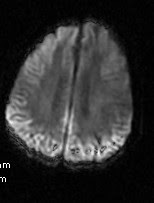

Among certain populations, such as libyan jews, rates are somewhat higher. The 'heidenhain variant' is a subclass of patients with cjd, who present with isolated visual symptoms at the onset without any cognitive decline. Sporadic, familial, iatrogenic and variant. Standard diagnostic tests will include a spinal tap to rule out more common causes of dementia and an electroencephalogram (eeg) to record the brain's electrical pattern, which can be particularly valuable.